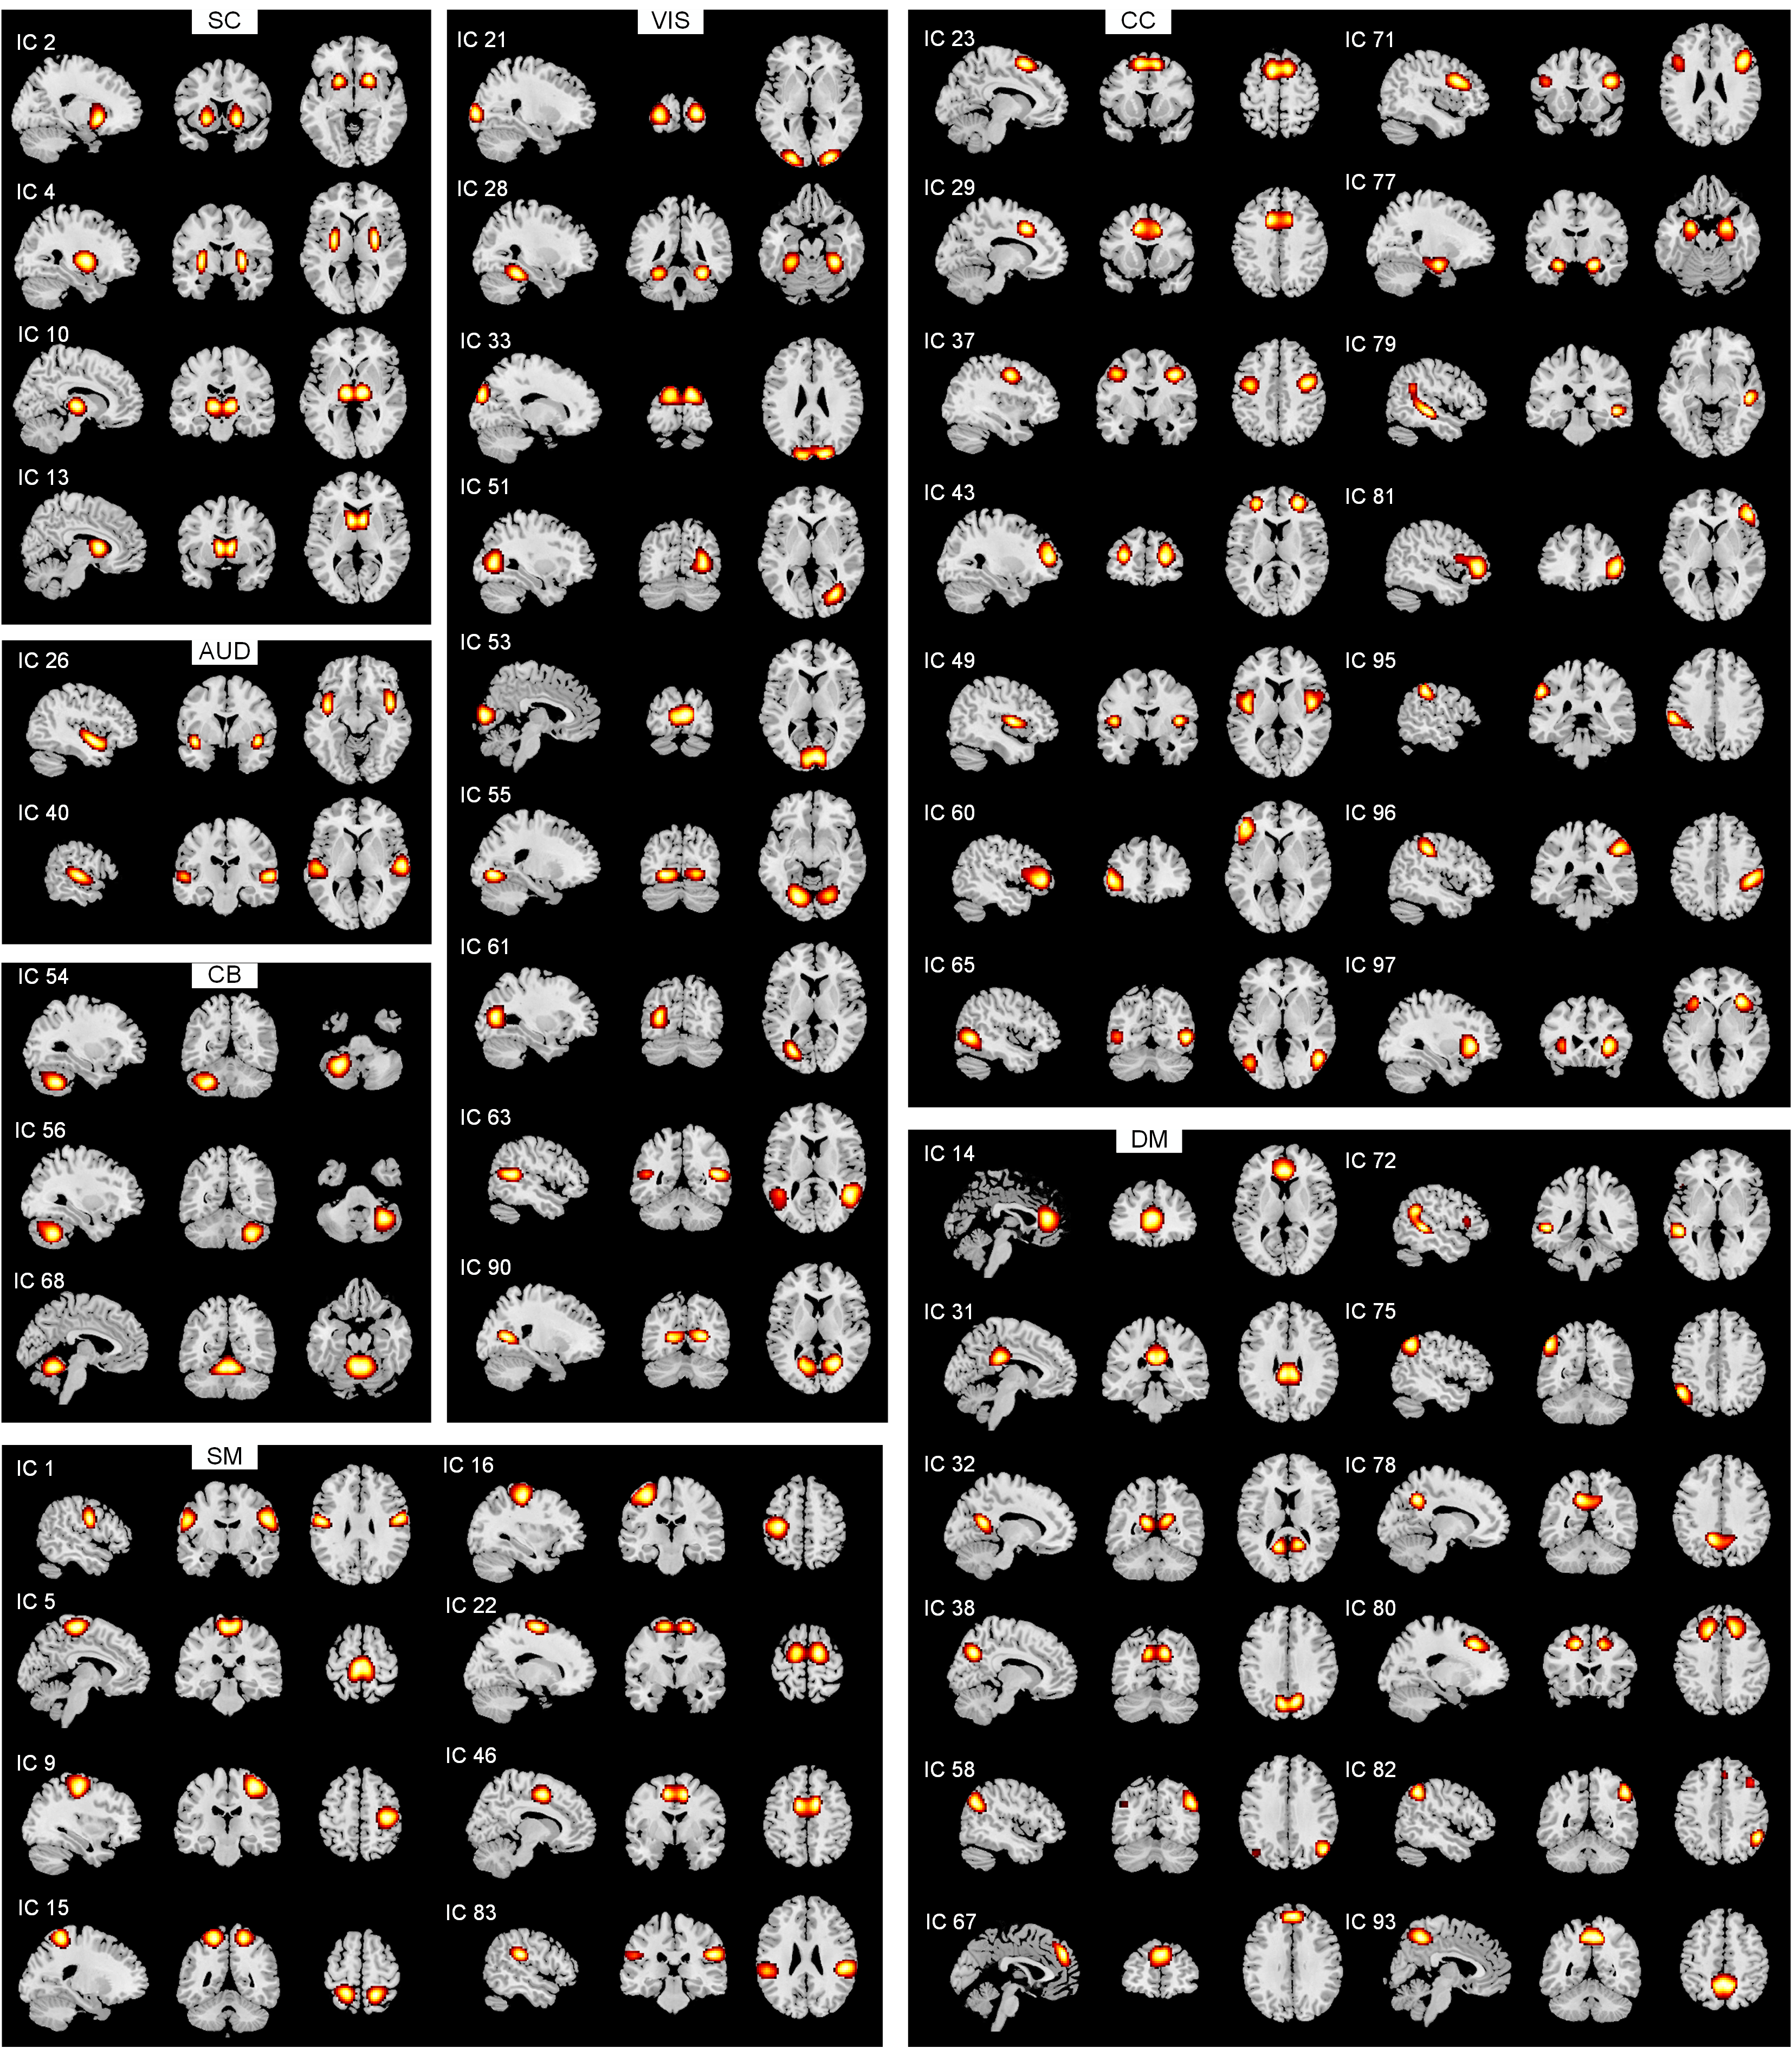

ALLEN E A, ERHARDT E B, DAMARAJU E, et al. A baseline for the multivariate comparison of resting-state networks[J]. Front Syst Neurosci, 2011, 5: 2.

doi: 10.3389/fnsys.2011.00002

pmid: 21442040